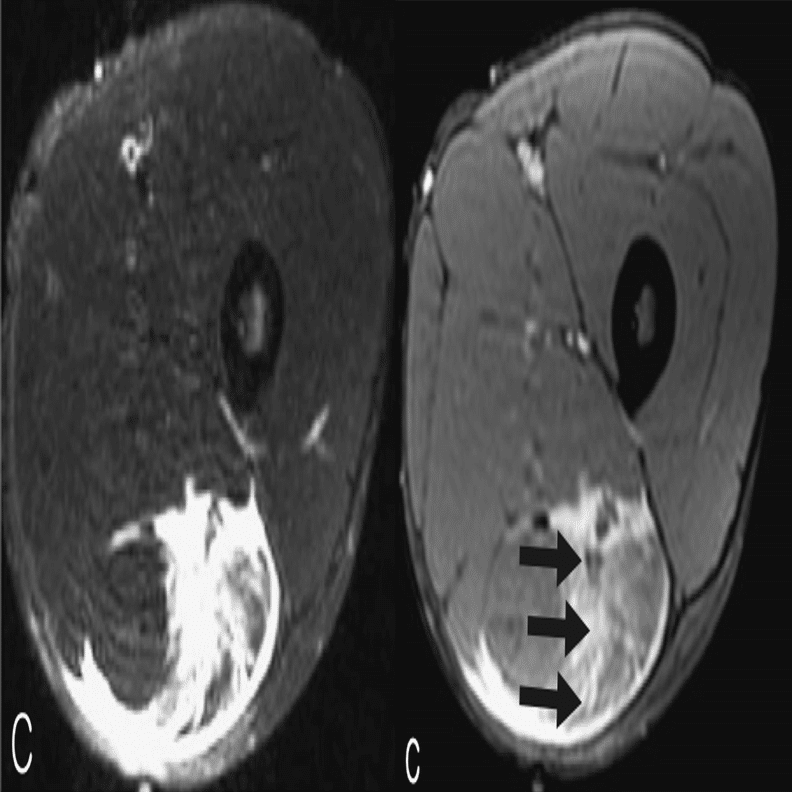

・Ⅱ型2度

(Pedret C, J Belg Soc Radiol. 2022から引用)

腱膜の連続性が背側部に途絶

(奥脇 透:大腿二頭筋肉ばなれの MRI 分類、臨床スポーツ、2019より引用)